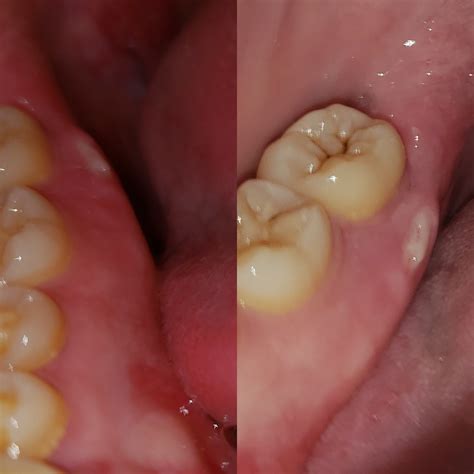

Bunion Surgery – Myths vs Reality - Bunion Surgeon London